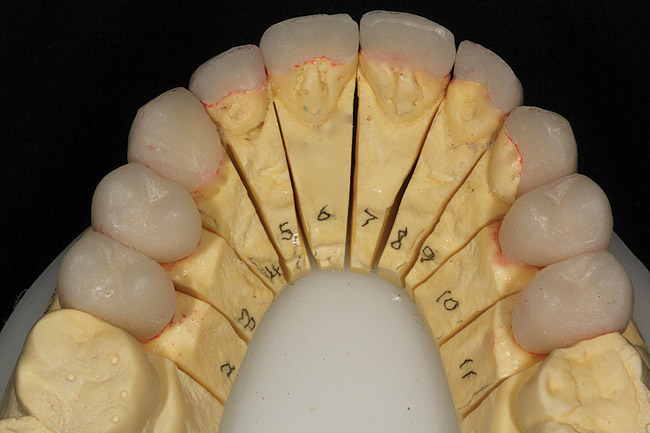

Figure 25  Through the lost-wax process, the IPS e.max restorations were pressed and then fitted to the master dies.

Figure 25

Figure 26  View of the lingual aspect of the fitted IPS e.max restorations on the master dies.

Figure 26

After receiving the provisional records, impressions, and eyebrow-to-chin photographs of the patient smiling with the provisionals in place (fabricated in plastic), a Sil-Tech® (Ivoclar Vivadent) matrix was formed over the cast of the provisionals and placed in a pressure chamber. This matrix then was used as a mold to inject wax onto the treated and lubricated master dies (Figure 24). Through the lost-wax process, the final restorations were produced using IPS e.max Press lithium-disilicate glass-ceramic. Impulse V1 was pressed at a temperature of 915° C (Figure 25 and Figure 26.).